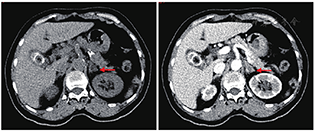

超声心动图:左房扩大(前后径43 mm),左室壁增厚(13 mm),左室舒张功能减低。双肾及肾血管超声:左肾内动脉血流阻力指数0.77(增高),余正常。肾上腺平扫增强CT:左侧肾上腺增粗,局部结节样,增强扫描边缘可见强化,径约1.4 cm,腺瘤?(图1)。